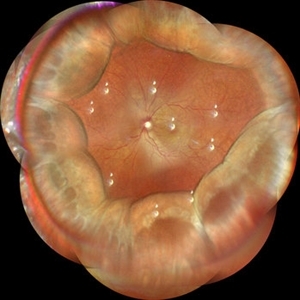

Uveal Effusion Syndrome

Uveal Effusion Syndrome

Oct 23 2023 by Gustavo Aguirre-Suarez

Fundus photograph of a 58-year-old man with Type 1 Uveal Effusion Syndrome, showing 360º bullous choroidal detachment.

Photographer: Dr. Gustavo Aguirre-Suarez

Imaging device: Zeiss Clarus 700

Condition/keywords: choroidal effusion, idiopathic uveal effusion syndrome